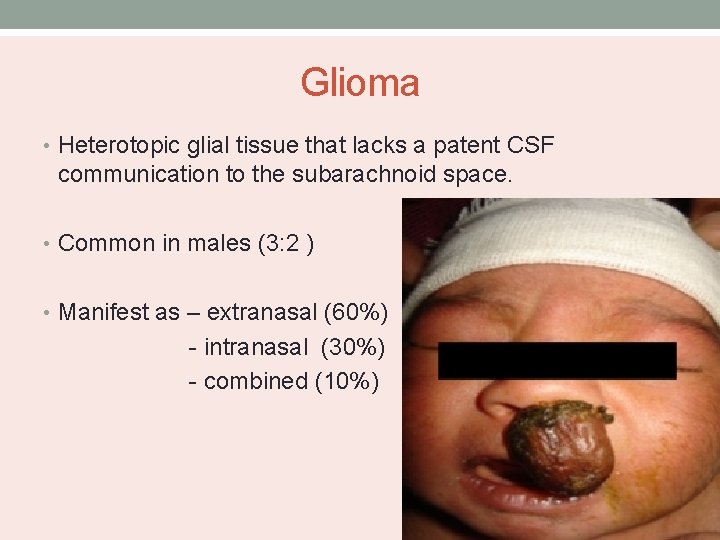

Glioma • Heterotopic glial tissue that lacks a patent CSF communication to the subarachnoid space. • Common in males (3: 2 ) • Manifest as – extranasal (60%) - intranasal (30%) - combined (10%)

• Extranasal – smooth, firm, non-compressible, occur along the side of the nose, glabella or nasomaxillary suture line. • Intranasal - pale mass within the nasal cavity with protrusion from the nostril and nasal obstruction. • Arises from the lateral nasal wall near the middle turbinate. • Do not change in size with crying or straining and do not transilluminate.

Investigation • CT scan to assess the bony anatomy of skull base. • MRI – soft tissue connection to brain. • Nasal endoscopy – to assess the location, extent and origin.

Management • Early surgical intervention • Extranasal – lateral rhinotomy, external rhinoplasty. • Intranasal – removed endoscopically